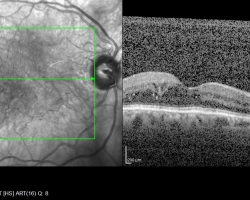

• OCT (2018)

œdème maculaire diabétique bilatéral